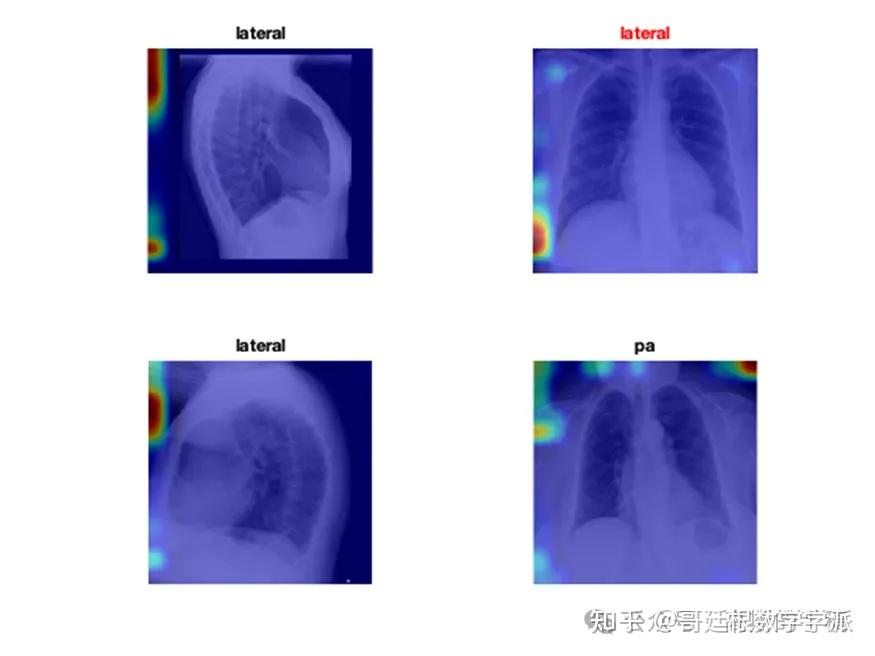

医学图像的深度学习可解释性(MATLAB R2021B)